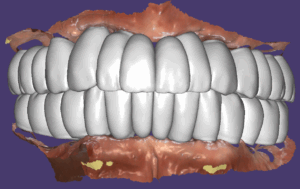

수술후 5개월차에 2차를 진행했습니다. 교합이 불안정해서 이 분은 스캔을 해서 맞춤지대주를 만들고 최종모양의 보철을 PMMA재료로 밀링해서 2차 당일에 끼워드렸습니다.

그렇게 한 이유는 교합안정성을 확보한 후 최종보철을 끼우기 위함이었어요.

PMMA로 3개월 정도 적응해 보도록 했습니다.

고경을 조절해 준 디자인

2차 하러 오신 날 최종보철의 형태를 임시치아 재료로 끼고 잘 생활하시다가 3개월 체크할 때 환자분이 편안하다고 하셔서 미리 만들어 놓은 지르코니아 보철로 교체해서 세팅한 모습입니다.